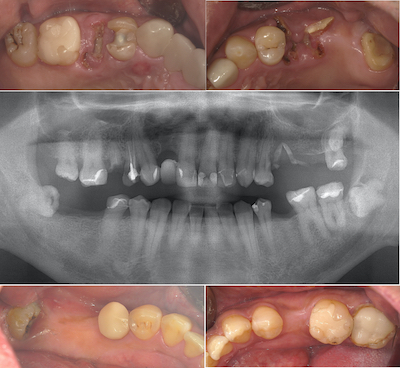

各々の部分の比較です。まず右上です。

右上のアンカースクリューによる圧下の結果のレントゲンです。

左上です。

左下です。

右下です。

初診時と術後のレントゲンです。